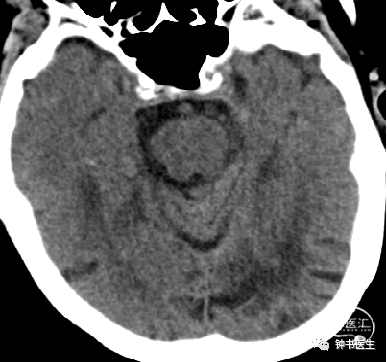

2019-1-10 当地CT

2019-1-12 当地CT

2019-1-13

2019-1-14

2019-1-16